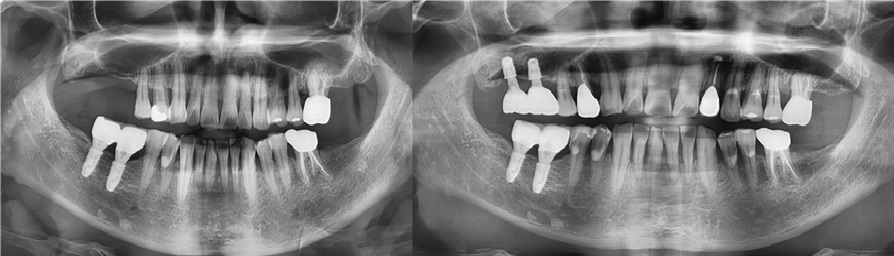

치료전후사진